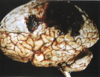

Figura 28.41 - Enf. de Huntington, hemisfério normal (izquierda) comparado con un hemisferio con **enfermedad de Huntington (derecha)** en el que se observa **atrofia del cuerpo estriado y dilatación ventricular**. Recuadro. Inclusiones intranucleares en las neuronas destacadas mediante tinción inmunohistoquímica para ubicuitina